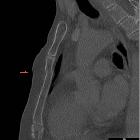

Atemartefakt

in sagittaler CT-Rekonstruktion bei Polytrauma: Die Unterbrechung im oberen Anteil des Corpus sterni könnte mit einer Fraktur verwechselt werden. Die Verwerfung der Hautkontur auf gleicher Höhe löst diesen Verdacht als Atemartefakt auf. Weitere Atembewegungen weiter kaudal.